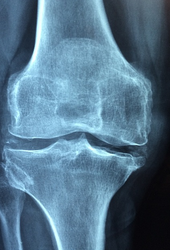

- 관절염 예방 및 완화: MSM은 관절연골의 손상을 줄이고, 염증을 억제하며, 통증을 완화하는 작용을 합니다. 여러 연구에서 MSM이 관절염 환자의 증상을 개선하는 것을 보여주었습니다. 예를 들어, 2006년 한 연구에서는 12주간 MSM 3g을 복용한 관절염 환자들이 통증과 염증이 감소하고, 관절 기능이 향상되는 것을 발견했습니다.